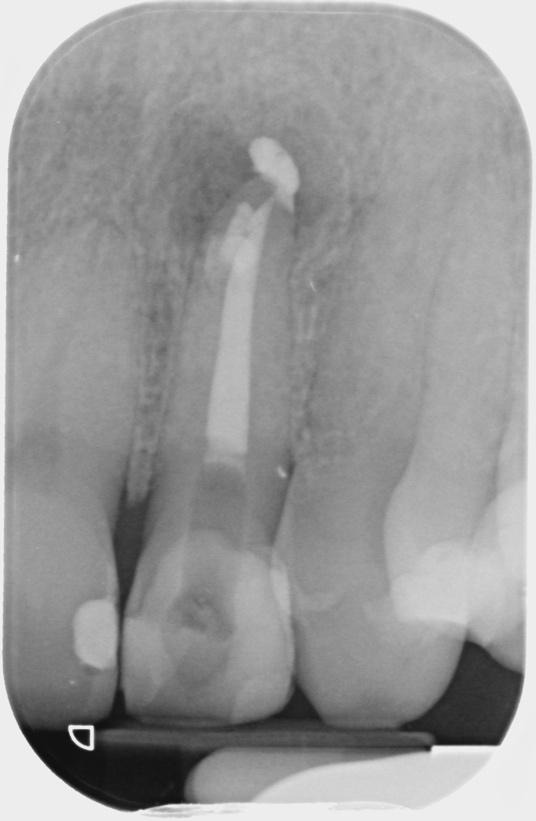

Pre-op IOPA and CBCT of the UR1 and UL2 looked like this:

Key findings from CBCT Consultant radiologist’s report by JM Radiology:

UR1

- Root filling under condensed.

- Large PARL (approx. 5mm) causing dehiscence of buccal cortex.

- Coronal one third of canal demonstrates some widening – likely to be anatomical rather than resorption and was mirrored on the UL1.

- No evidence of a fracture.

UL2

- Root filling a little under condensed.

- Large PARL; 6.5mm in diameter and dehiscence of the buccal cortex.